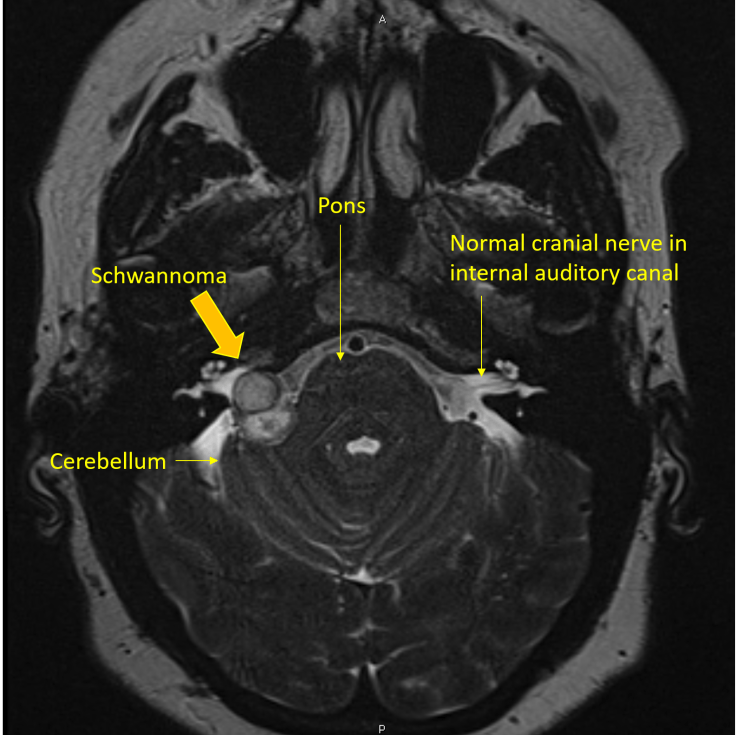

Intracranial schwannomas most commonly arise from the vestibular portion of the Vestibulocochlear nerve (cranial nerve VIII). The central/proximal aspect of the nerve is myelinated by oligodendroglial cells whereas the distal/peripheral aspect is myelinated by Schwann cells. These distally located Schwann cells give rise to vestibular schwannomas that originate in the distal aspect of the nerve, usually within the internal auditory canal where it normally courses. Tumor growth is often restricted until it exits the bony confines of the canal and enters the comparative spaciousness of the cerebellopontine angle, where it is able to form a bulbous mass like the one shown here. Vestibular schwannomas are the most common neoplasms to involve the cerebellopontine angle and should be highly considered in the differential of any extra-axial lesion seen in this location.